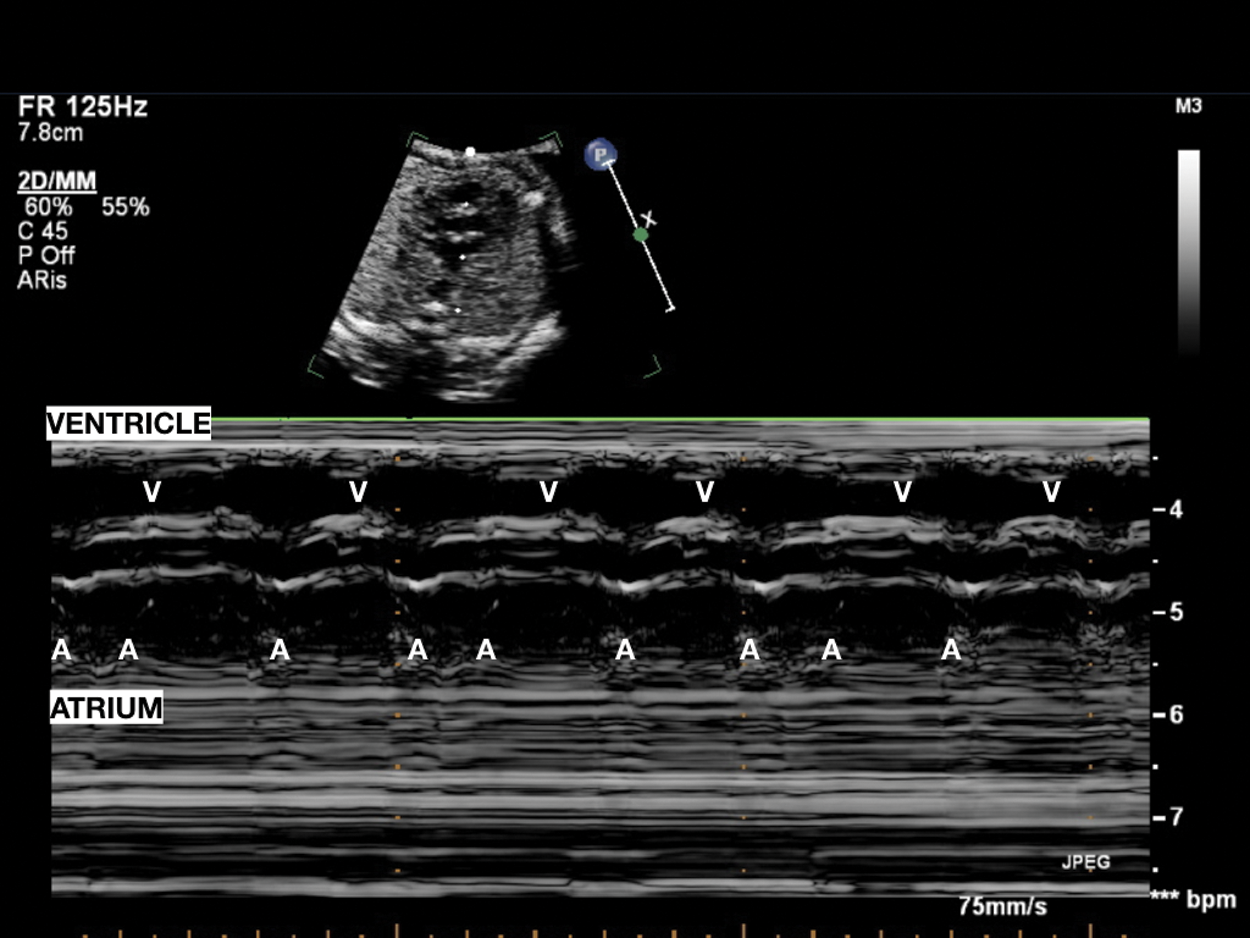

Figure 3: Pseudobradycardia: Atrial bigeminy with blocked premature beats; atrial rhythm with an alternating, shorter–longer AA time interval induces low ventricular heart rate

Figure 4: Pulsed-wave Doppler recording from the LV inflow and LV outflow in a fetus with atrial bigeminy. One atrial is conducted, but PAC occurred sooner, and the inflow Doppler waveform showed only an A wave since it occurred earlier and fused with the E wave. There is a ventricular contraction following this PAC, indicating the PAC is conducted. A, atrial contractions; LV, left ventricle, V, ventricular contractions; PAC, premature atrial contraction

Blocked PAC can occur at regular intervals and last over long period of time leading to persistent fetal bradycardia. The typical pattern of regular bradycardia due to ectopic beats corresponds to blocked atrial bigeminy and produces FHR between 75 and 90 bpm when conduction is in a 2:1 AV pattern. It is a common cause of regular bradycardia and management is the same as for isolated PAC. The risk of supraventricular tachycardia is about 10% of fetal atrial bigeminy with block [2]. Fetal echocardiography is recommended to assess cardiac structure and weekly FHR. Persistent atrial bigeminy can be confused with pathological 2:1 AVB.

Differential diagnosis is essential for therapeutic strategies, because long lasting 2:1 AV block has severe consequences. Echocardiography allows to evaluate FHR and regularity of atrial and ventricular systolic events and the AV relationship through M-mode (Fig. 3) and Pulsed-wave Doppler method (Fig. 4). However, it is often complex to distinguish 2:1 AVB from prolonged atrial bigeminy using only echocardiography: Lately, the more routine use of fetal magnetocardiography (see later) allows precise and rapid differential diagnosis [21].

Pulsed Doppler (Figs. 4–12) recordings of simultaneous left ventricular inflow and outflow, superior vena cava and ascending aortic flow, or pulmonary artery and pulmonary venous flow permit documentation of the relationship between mechanical atrial and ventricular systole [6].